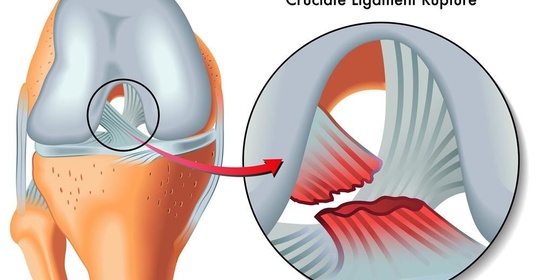

單神經病變變與神經叢神經病變變:症狀、病因、看醫生、檢查、治療